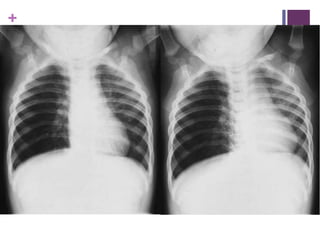

DDx CCF

 Similar Wheeze and resp distress without

infective symptoms

 From newly Dx Congenital Heart Disease, or

arrhythmias

 CHD Multiple types:

 Transposition of great vessels

 Pulmonary/Aortic stenosis

 Hypoplastic left heart

 Tetrallogy of Fallot